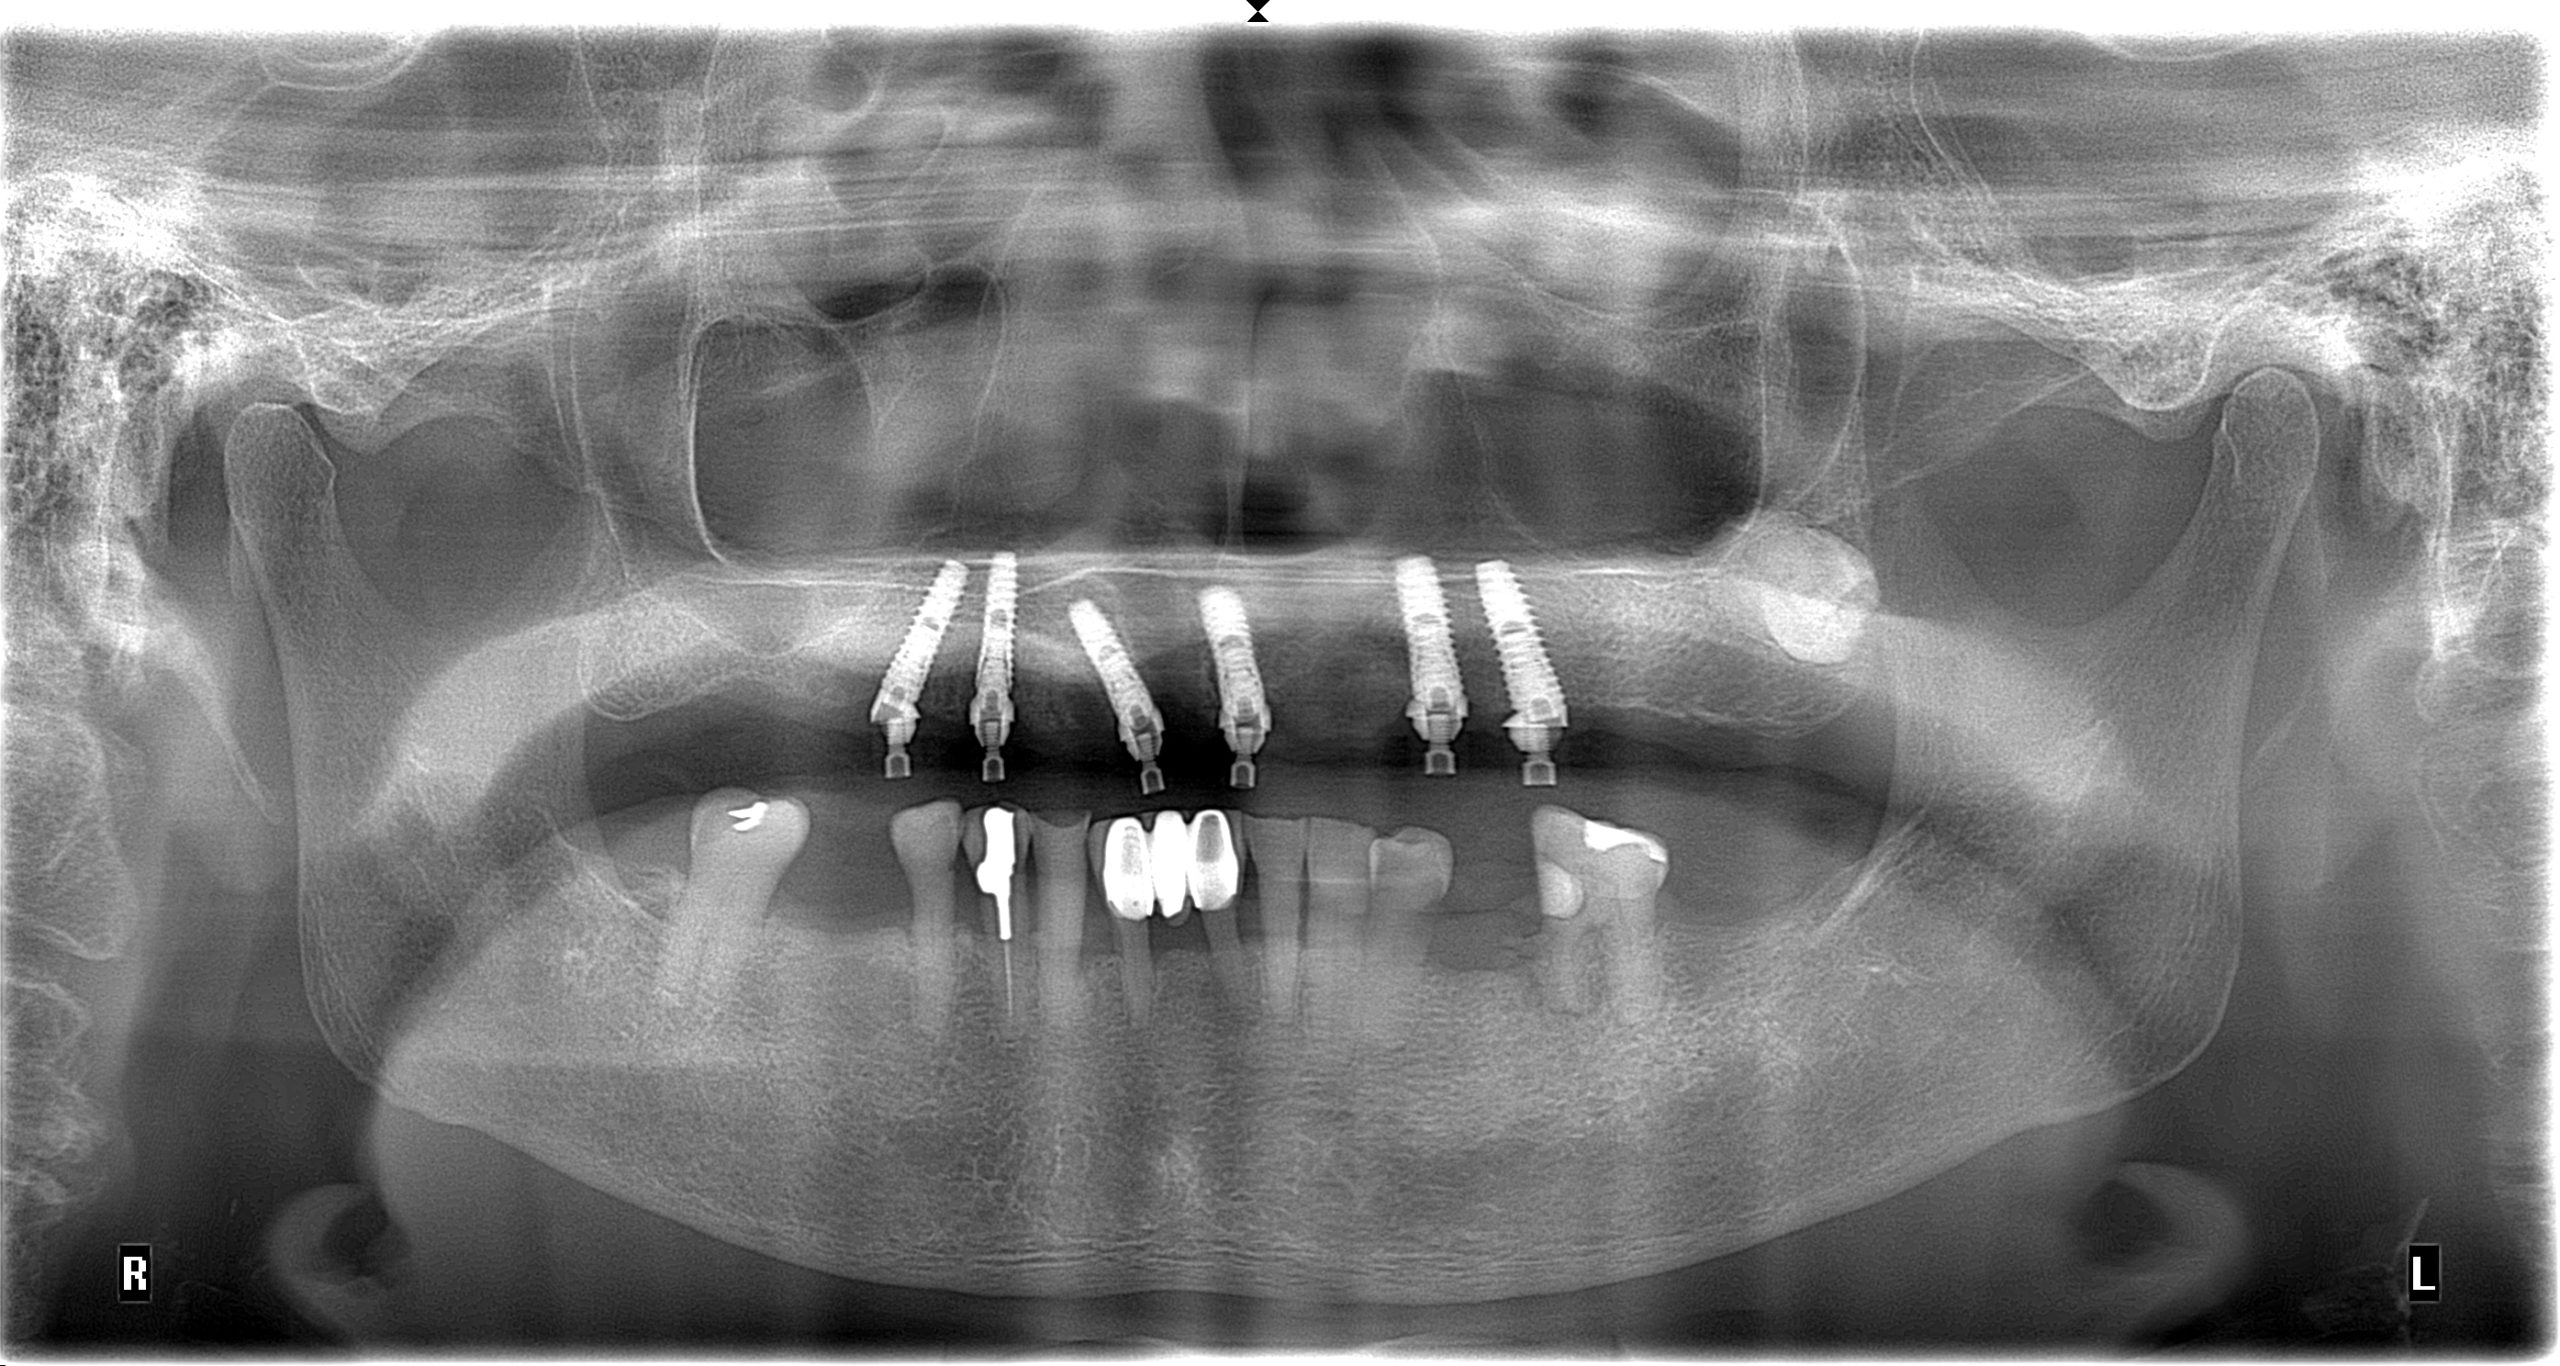

Upper Jaw All-on-6 Replacing Existing Full Denture